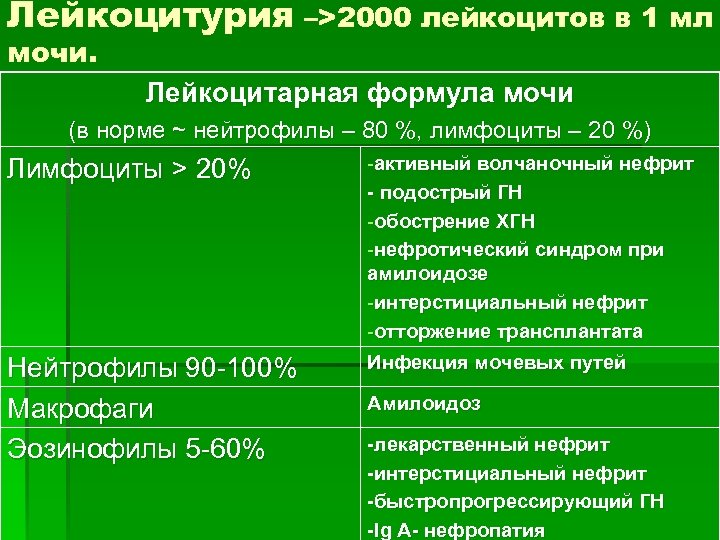

Лейкоцитурия –>2000 лейкоцитов в 1 мл мочи. Лейкоцитарная формула мочи (в норме ~ нейтрофилы – 80 %, лимфоциты – 20 %) Лимфоциты > 20% Нейтрофилы 90 -100% Макрофаги Эозинофилы 5 -60% -активный волчаночный нефрит - подострый ГН -обострение ХГН -нефротический синдром при амилоидозе -интерстициальный нефрит -отторжение трансплантата Инфекция мочевых путей Амилоидоз -лекарственный нефрит -интерстициальный нефрит -быстропрогрессирующий ГН -Ig A- нефропатия